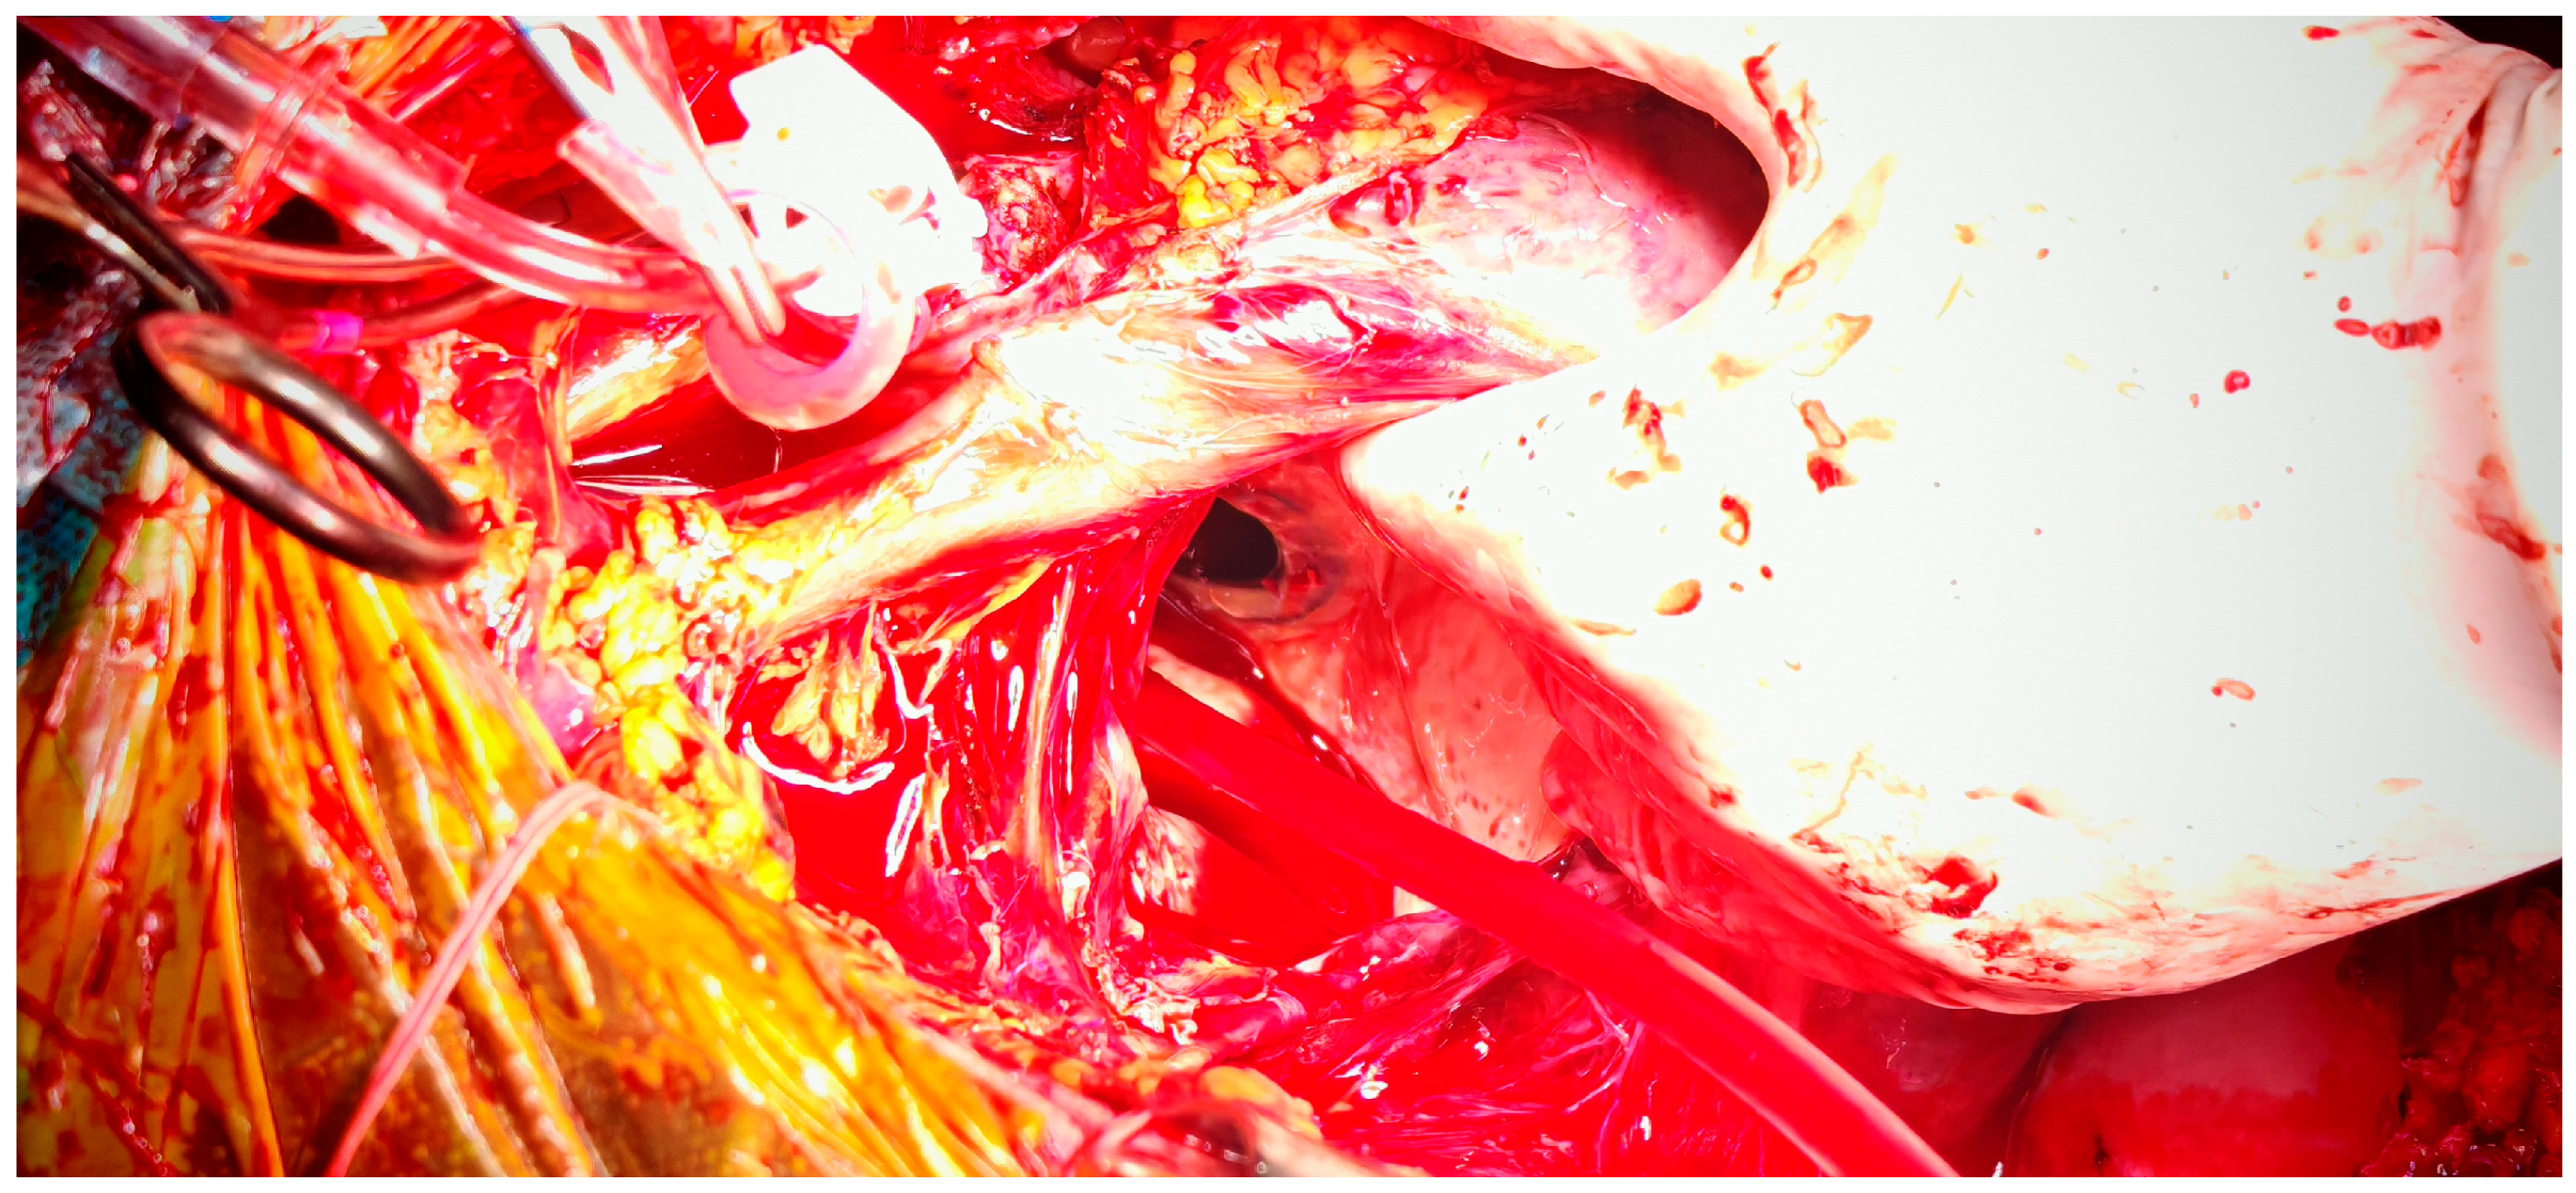

4. Case Presentation